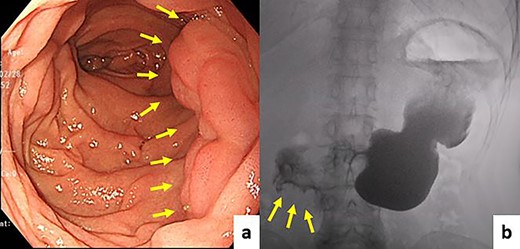

A 63-year-old woman was found to have a 7 × 8 mm, 0–IIc type tumor on the opposite side of the duodenal papilla in the follow-up EGD after endoscopic submucosal dissection for early gastric cancer (Fig. 3a). The pathological diagnosis was well-differentiated adenocarcinoma (Fig. 3b). CT revealed no lymph node metastasis or distant metastasis (Fig. 3c). We diagnosed early duodenal cancer as cT1aN0M0 (TNM classification). We planned to perform partial duodenectomy first and then pancreatoduodenectomy secondarily if the pathological examination of the resected specimen showed advanced duodenal cancer. After the duodenectomy, pedicled jejunal flap reconstruction was performed in the same manner as in Case 1. The pathological diagnosis was early duodenal cancer (pTisN0M0Stage0). The patient was discharged on the ninth postoperative day without any surgical complications. No tumor recurrence or gastrointestinal symptoms were reported 14 months after surgery. Follow-up EGD and upper gastrointestinal radiography did not show any signs of stenosis or motility disorder (Fig. 4a and b).

(a) EGD showing a 0–IIc type tumor on the opposite side of the duodenal papilla. (b) Pathological diagnosis was well-differentiated adenocarcinoma (hematoxylin and eosin ×40). (c) CT revealed some clips taken after tumor biopsy as a hyperdense area.

Follow-up EGD and upper gastrointestinal radiography did not show stenosis, diverticulum, or motility disorder. (a) EGD, (b) upper gastrointestinal radiography.